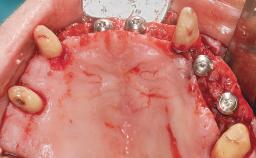

Immediate Loading of Six Implants in the Maxilla and Final Restoration with a Full-Arch CAD/CAM Zirconia FDP

A 63-year-old male patient was referred for a consultation and treatment of partial edentulism in the maxilla. The patient presented with residual anterior teeth and declined a partial removable prosthesis. He reported that the maxillary posterior teeth had been extracted due to mobility and periodontal disease two months before the consultation. The patient’s chief complaint was that his residual maxillary teeth were mobile and that he was unable to chew. The patient’s desire was a stable and comfortable fixed maxillary rehabilitation. The patient was a light smoker (fewer than 10 cigarettes/ day), and his medical history was without significant findings. He was not on any regular medication at the time of consultation. The extraoral examination revealed a normal physiognomy with a correct distribution of the facial thirds. The patient presented a low lip line, and the transition line between teeth and soft tissues was not exposed during a forced smile.

# of Implants 6

Type of Implants One-Piece

Bone Augmentation Horizontal|Simultaneous

Defining Characteristics Fully edentulous upper jaw to be rehabilitated with four or more implants

Modality 6+ implants with immediate loading